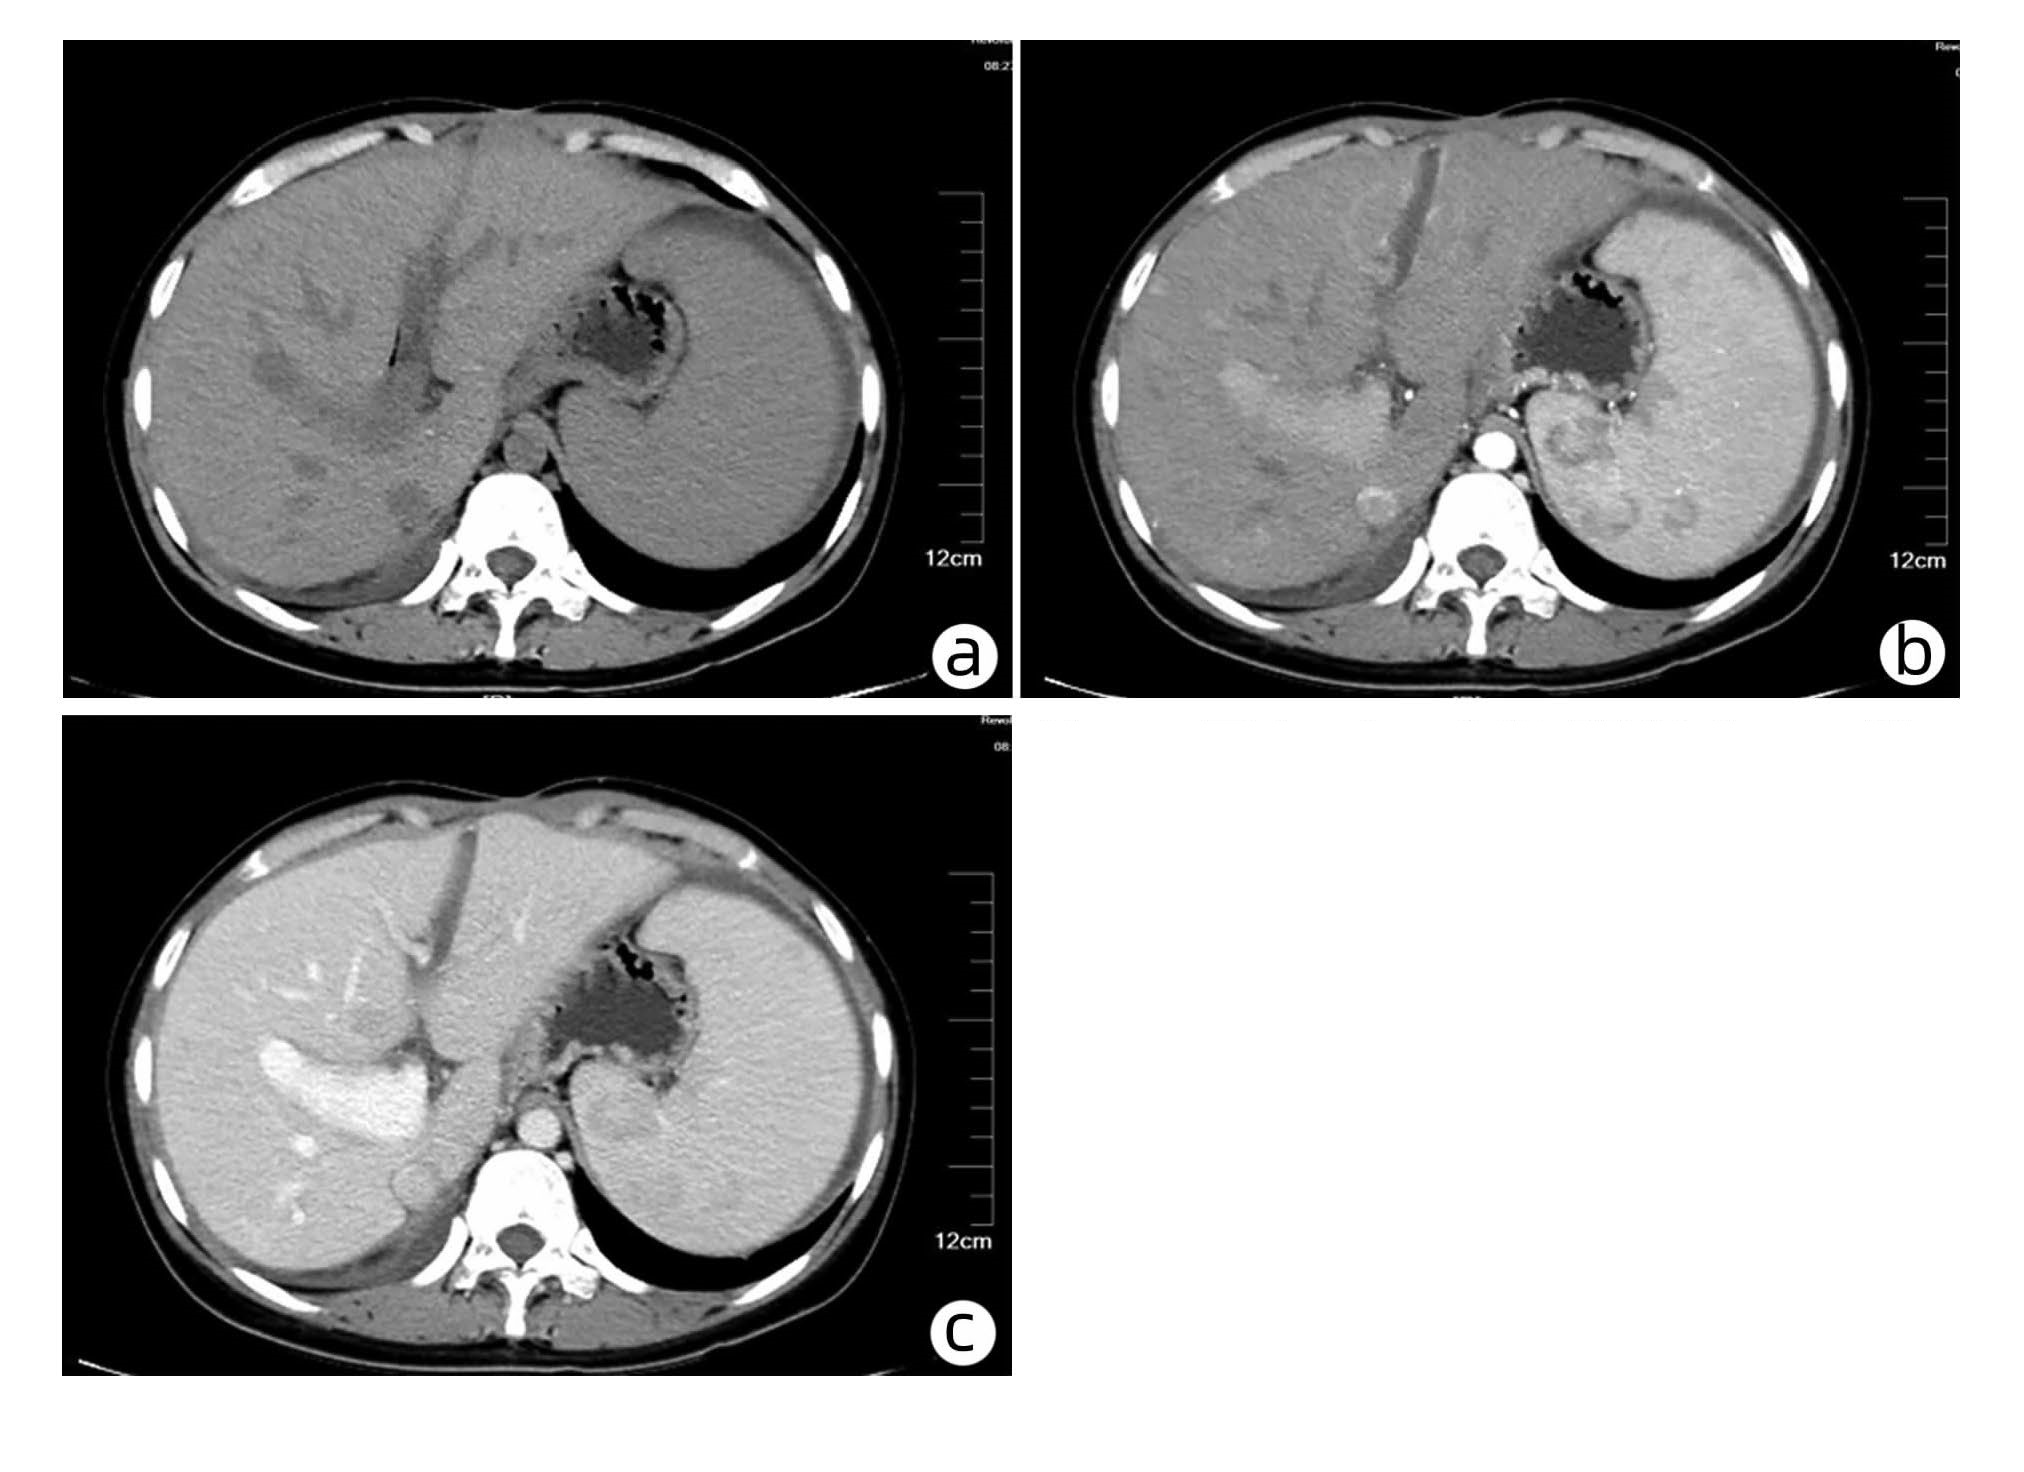

Efficacy of hepatic arterial infusion chemotherapy and its multimodality therapeutic regimens in treatment of patients with advanced hepatocellular carcinoma and related prognostic factors

Wencong DAI, Mengya ZANG, Guosheng YUAN, Qi LI, Rong LI, Wenli LI, Shuyu DONG, Jinzhang CHEN

2023, 39(7): 1592-1599. DOI: 10.3969/j.issn.1001-5256.2023.07.013

Abstract(1478) HTML (1038) PDF (2254KB)(93)

Abstract:

Objective  To investigate the efficacy of continuous hepatic arterial infusion chemotherapy (HAIC) with the FOLFOX regimen and its multimodality therapeutic regimen in the treatment of patients with advanced hepatocellular carcinoma, as well as the influencing factors for prognosis.  Methods  A retrospective analysis was performed for the clinical data of 66 patients with advanced hepatocellular carcinoma who received continuous HAIC with FOLFOX regimen in Nanfang Hospital, Southern Medical University, from September 2018 to November 2021. The patients were observed in terms of objective response rate (ORR), disease control rate (DCR), median progression-free survival (mPFS), and median overall survival (mOS) after treatment, and treatment-related adverse reactions were recorded. For the patients with portal vein tumor thrombus, the effect of the treatment on portal vein tumor thrombus was assessed. The Kaplan-Meier method was used for survival analysis, and the Cox regression analysis was used to investigate the influencing factors for prognosis.  Results  According to the RECIST1.1 criteria, FOLFOX-HAIC and its multimodality therapeutic regimen achieved an ORR of 33.3% (22/66) and a DCR of 86.4% (57/66) in the treatment of 66 patients with advanced hepatocellular carcinoma, with an mPFS time of 8.2 months and an mOS time of 22.1 months. Among the 39 patients with portal vein tumor thrombus, 2 achieved complete remission, 8 achieved partial remission, 24 achieved stable disease, and 5 had disease progression, with an ORR of 25.6% (10/39) and a DCR of 87.2% (34/39). The main adverse reactions included gastrointestinal reactions (16.7%, 11/66), pyrexia (12.1%, 8/66), liver area pain (10.6%, 7/66), bone marrow suppression (3.0%, 2/66), and contrast agent allergy (3.0%, 2/66), and there were no grade > Ⅳ toxic or side effects or deaths caused by such complications. The Cox regression analysis showed that extrahepatic metastasis (hazard ratio [HR]=2.668, 95% confidence interval [CI]: 1.357-5.245, P < 0.05) and prothrombin time (PT) (HR=1.282, 95%CI: 1.080-1.630, P < 0.05) were independent risk factors for PFS, and aspartate aminotransferase level (HR=1.008, 95%CI: 1.002-1.013, P < 0.05) and PT (HR=1.303, 95%CI: 1.046-1.630, P < 0.05) were independent risk factors for OS.  Conclusion  FOLFOX-HAIC and its multimodality therapeutic regimen has a certain clinical effect with controllable adverse reactions in the treatment of advanced hepatocellular carcinoma.